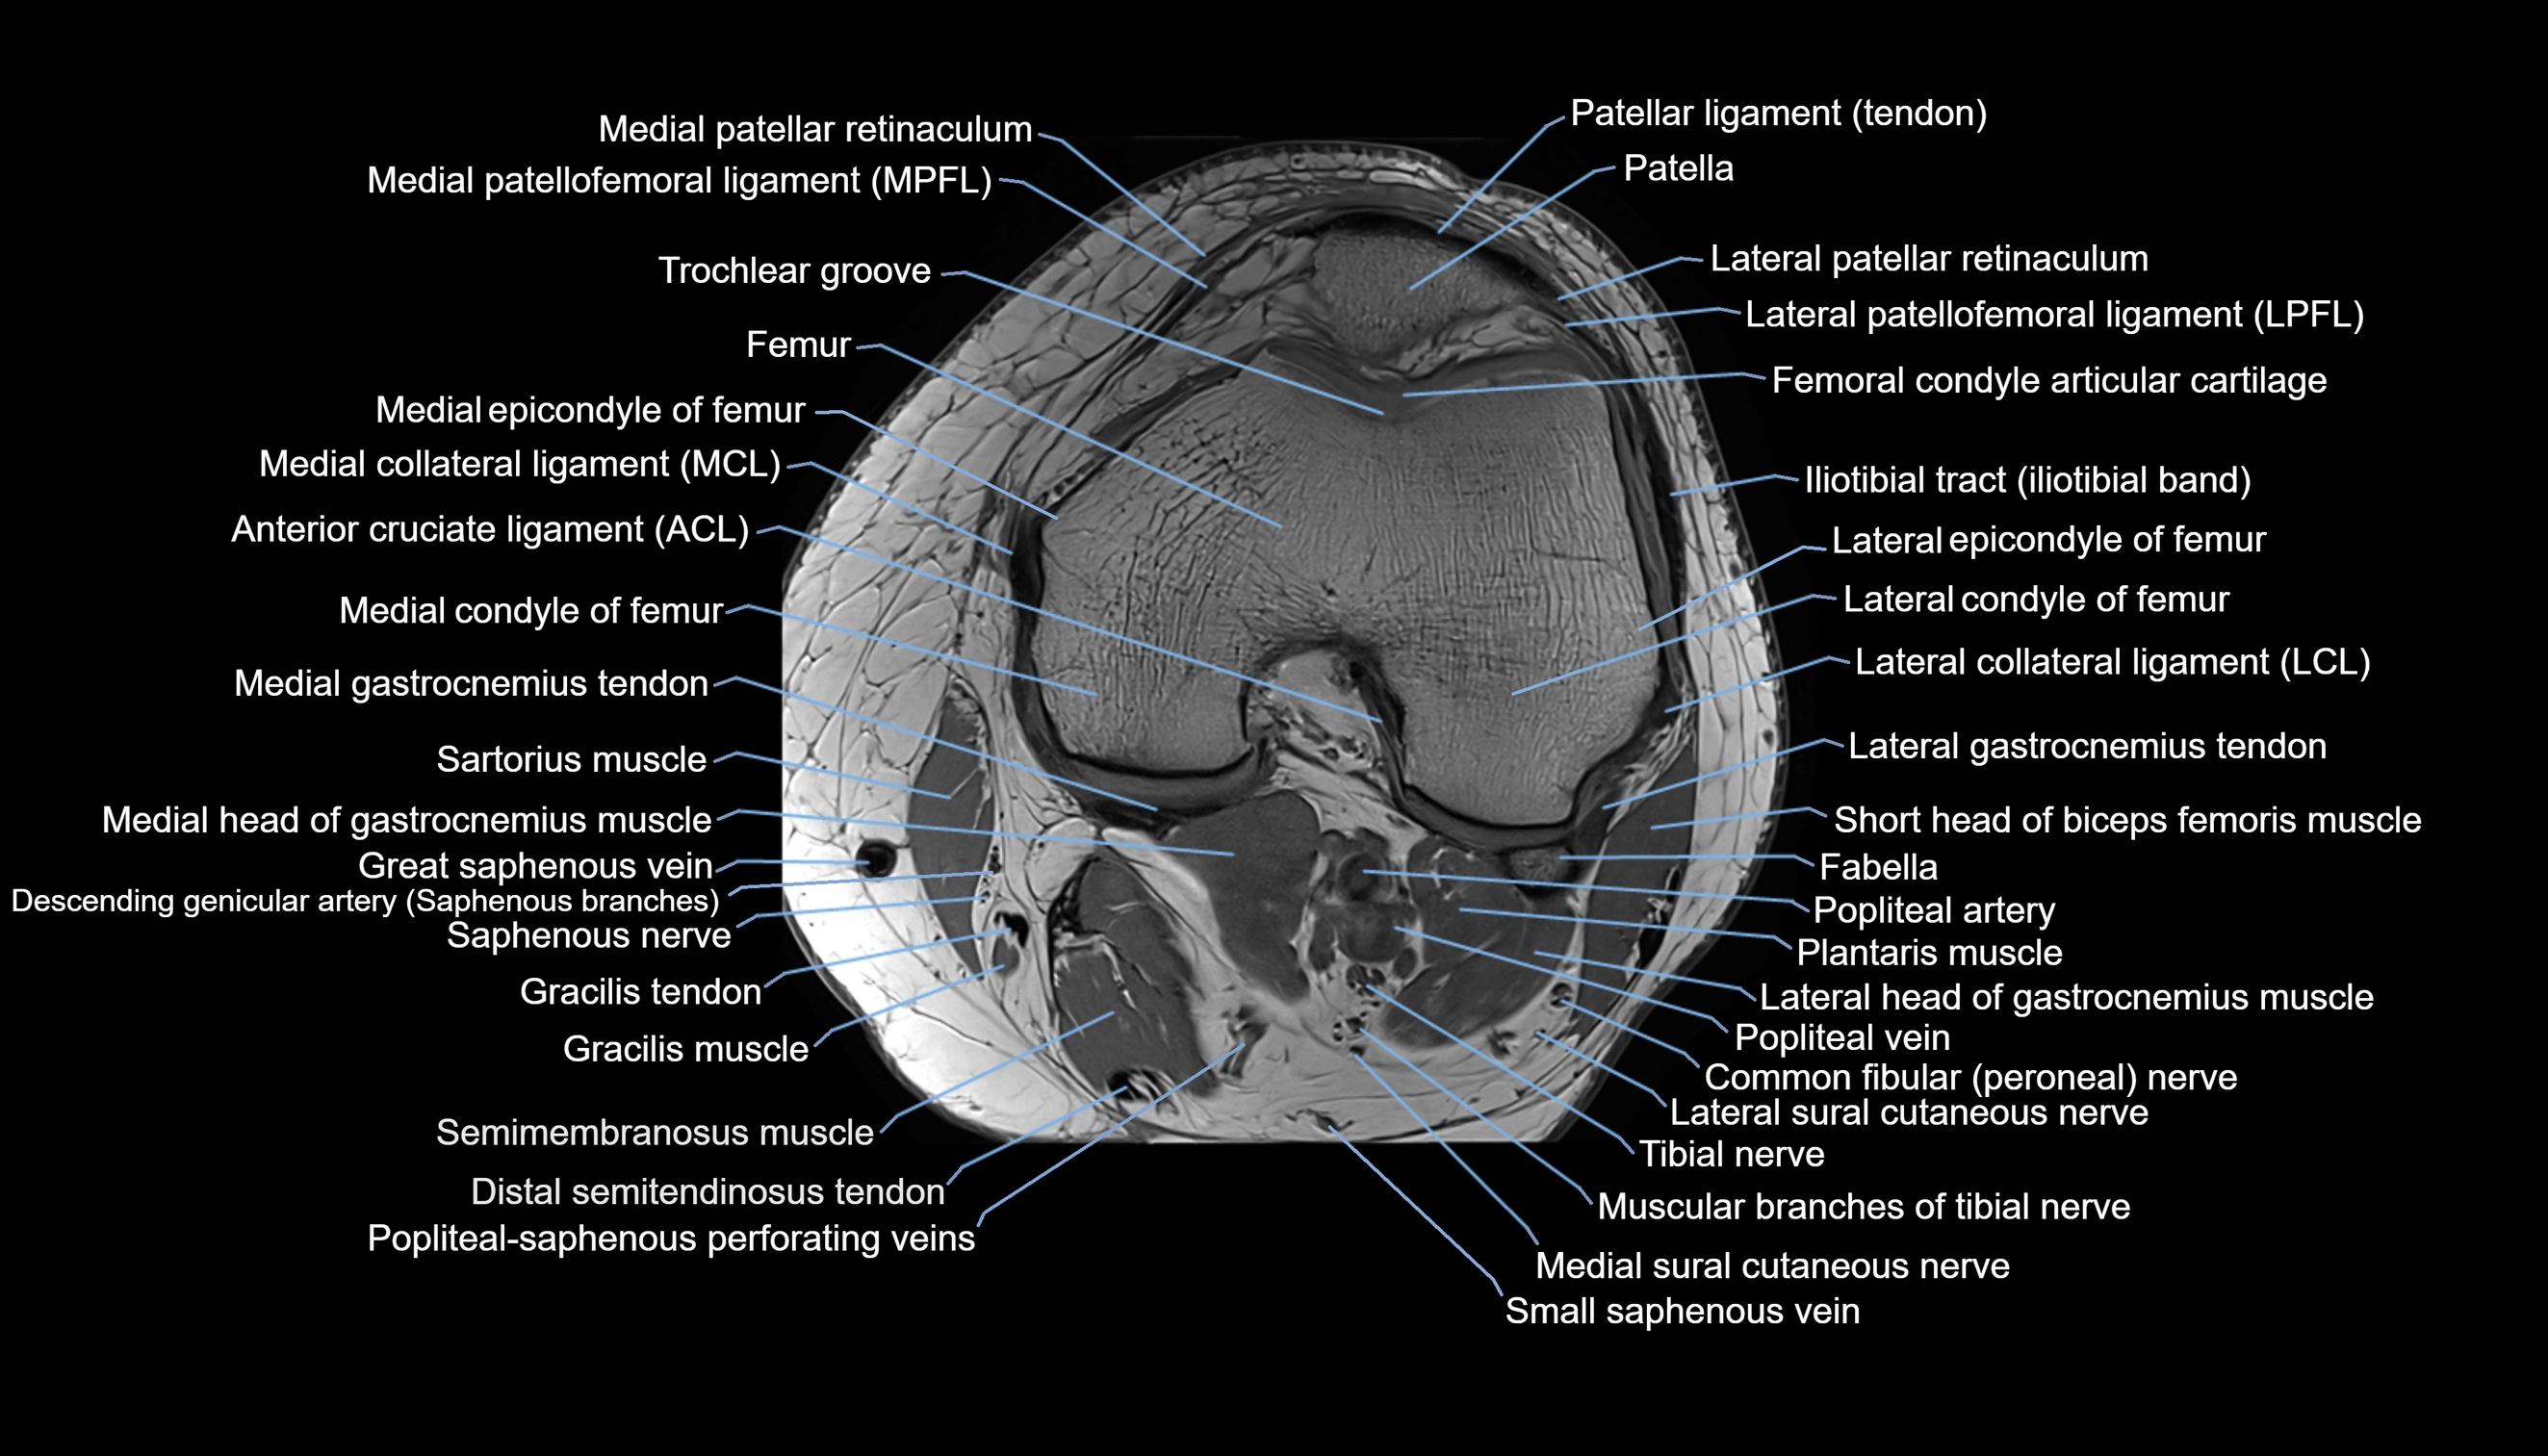

- Common fibular nerve

- Lateral collateral ligament

- Lateral condyle of femur

- Lateral epicondyle of femur

- Lateral sural cutaneous nerve

- Medial collateral ligament

- Medial condyle of femur

- Medial epicondyle of femur

- Medial gastrocnemius tendon

- Medial head of gastrocnemius muscle

- Medial patellar retinaculum

- Medial patellofemoral ligament

- Medial sural cutaneous nerve

- Muscular branches of tibial nerve

- Popliteal artery

- Popliteal vein

- Popliteal–Saphenous perforating veins

- Saphenous nerve

- Sartorius muscle

- Semimembranosus muscle

- Small saphenous vein

- Soleus muscle

- Tibial nerve